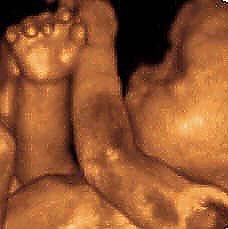

Die vierte Dimension (Foto: nnz)

Im Laufe der vergangenen zwanzig Jahre hat die Ultraschall-Diagnostik enorme Fortschritte gemacht. Jüngste Entwicklung ist die 4D-Sonographie, die im Rahmen der Ultraschallbehandlung erst an wenigen Kliniken möglich ist. Während im herkömmlichen 2D-Standard die inneren Organe des Kindes, wie Herz, Leber, Nieren, Hirn etc., ausreichend dargestellt werden, können durch die 3. Dimension, also die 3D-Sonographie, die Strukturen plastisch gezeigt werden. Das Bild ist für den Laien wesentlich eindrucksvoller. Mit 4D wird die Hinzuziehung einer weiteren Dimension – der Zeit - bezeichnet.

Hier wird das Baby auch mit seinem Bewegungen räumlich und zeitgleich am Monitor dargestellt, womit sich die Untersuchungszeiten mit dieser Methode gegenüber der 3D-Sonographie drastisch verkürzen. Bei günstiger Lage des Kindes wird manchmal eine Qualität erreicht, die an ein Foto erinnert. Die neuen Geräte eröffnen die Möglichkeit, weitaus genauer und besser als bisher sowohl gynäkologische Tumore festzustellen wie auch in der pränatalen Medizin schneller und genauer den Befund zu diagnostizieren.